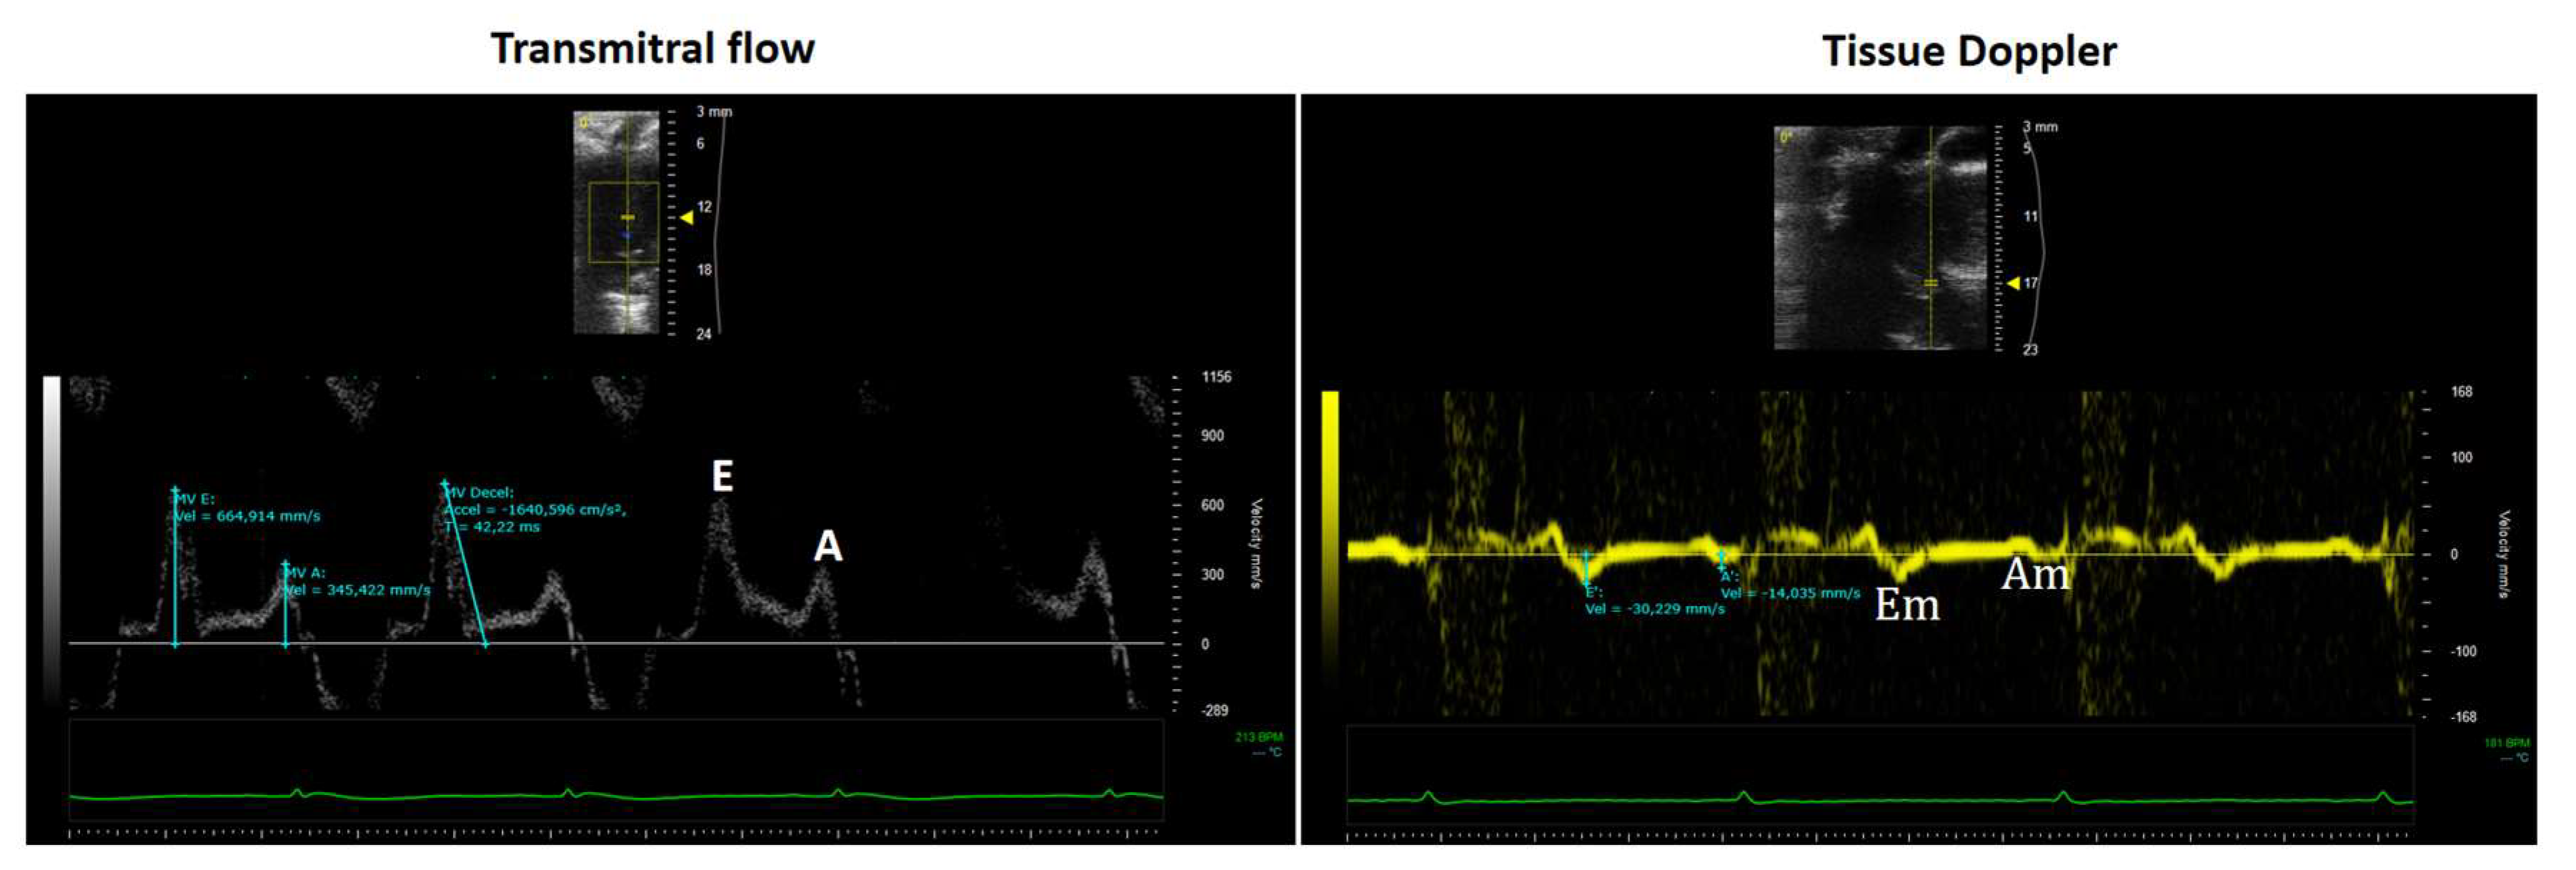

9. Role of Echocardiography in the Assessment of Left Ventricular Diastolic Function

- The E wave represents early diastolic filling driven by the pressure gradient between the left atrium and ventricle.

- The A wave corresponds to atrial contraction and the elastic recoil of the atrium and ventricle during late diastole.

- Mitral Annular Tissue Doppler Imaging (TDI)

- A positive systolic wave (Sm), and

- Two negative diastolic waves: early (Em) and late (Am).